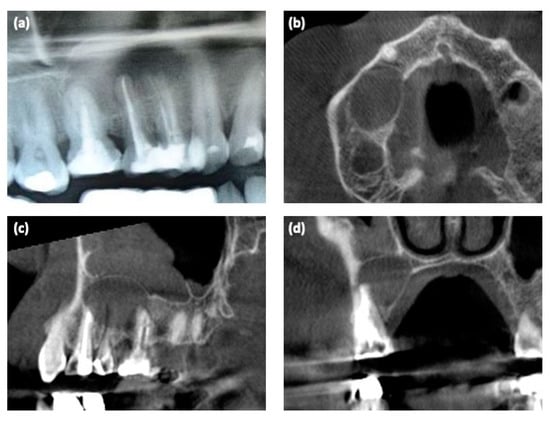

Six months postoperatively, the bone tissue healing was observed with dental X-ray (Figure 3a,b).

The second stage surgery was then performed; before implant placement, using a trephine bur, an alveolar bone sample was obtained from the #15 implant site (Figure 3c). Three implants (Blossom, Intra-lock, Birmingham, AL, USA) were placed in the area of teeth #14–16 (Figure 3d–f). The sample was processed and bone histomorphometry was performed (Figure 3g). Sutures were removed after 10 days.

Figure 3. (a,b) Six months post-surgical regeneration procedures, clinical and radiological view; (c) bone sample harvesting procedure at the #15 implant site using a trephine bur; (d) dental implant placement; (e,f) intraoral radiograph after placing dental implants; (g) the magnification of histological findings of the bone sample (osteoblastic cells on the surface of the new woven bone containing osteocytes).